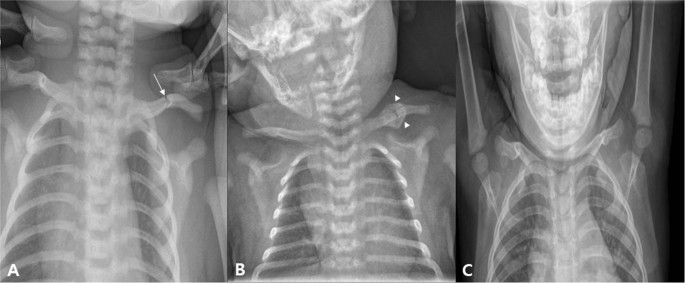

The incidence of clavicular fractures in newborns ranges from 0.01 to 1.65 percent, and the incidence of clavicular fracture in patients with CMT in the study of 996 patients with CMT was 2.01%6,20,21,22,23. Considering the prevalence of CMT, the prevalence of clavicle fractures in CMT patients is very low in infants as a whole. However, in our study, the incidence of clavicular fracture in patients with CMT was 11.19%. This is likely due to two reasons: First, we did not perform routine x-ray examinations for clavicular fractures in all CMT children, but performed in patients with suspected clavicular fractures on physical examination, such as decreased Moro reflex, swelling, mass, tenderness, and crepitation of the affected side. However, in our study, only CMT patients who received x-rays were enrolled; the incidence of clavicular fracture in CMT patients seems to be higher than in previous studies. Second, more complicated SCM patients tend to be admitted to our hospital, as they are referred from local primary clinics due to the nature of the medical system in Korea. However, considering the relatively high incidence rate of clavicular fracture in CMT patients and the association between clavicular fracture and increased body weight at birth, a more thorough evaluation seems necessary. In this study, only a conservative treatment was performed in CMT patients with clavicular fracture, except for the incorporation of stretching exercise and home education for CMT. On follow-up plain radiography, however, most of the CMT patients with clavicular fracture showed a tendency to recover well without deformation of the clavicle (Figs 3 and 4).

An infant who visited our hospital for left torticollis. In ultrasound examination, there was muscular fibromatosis in right SCM. (A) At 4 days after birth, left clavicular fracture was seen (arrow). (B) Follow-up plain radiograph at 21 days after birth. A callus formation was seen around fracture site of left clavicle (arrowhead). For clavicular fracture, only a conservative treatment was performed except stretching exercise and home education for right CMT. (C) Follow-up plain radiograph at 22 month after birth. Callus formation was disappeared, and it is difficult to find the difference between left and right clavicle. CMT; congenital muscular torticollis, SCM; sternocleidomastoid.